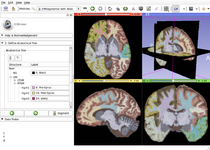

The community of Slicer developers is proud to announce the release of Slicer 4.0.

- Slicer 4.0 includes a major overhaul of the user interface, improved and simplified workflows for major tasks, simplified procedures for developers, and improved Python support.

Slicer is a community platform created for the purpose of subject specific image analysis and visualization.

- Multi-modality imaging including, MRI, CT, US, nuclear medicine, and microscopy